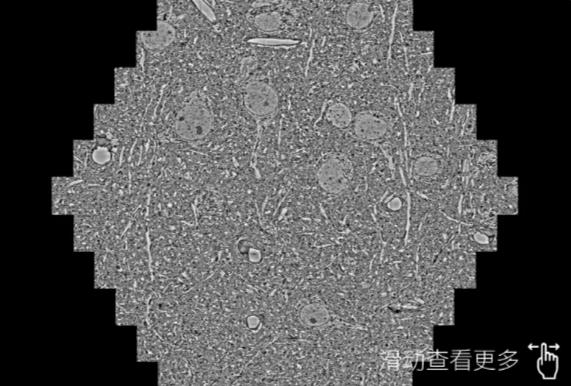

鼠脑切片。左图使用湛江蔡司湛江扫描电镜MultiSEM706对165μmx143pm面积区域成像,耗时仅需1.5秒。右图为鼠脑切片中30μm区域放大效果。样品由芝加哥大学B.Kasthuri提供。

使用蔡司高速湛江扫描电镜MultiSEM对1mm²人脑皮层组织进行高分辨成像,并对其中的各种细胞结构进行三维重构分析。左图展示了2x3mm²组织平面中锥体神经元的三维重构效果。右图显示了局部体积神经元三维重构。图像由哈佛大学chtman实验室提供,渲染图由D. Berger 制作。